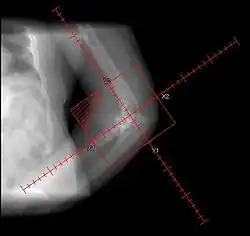

| Heterotopic ossification around the hip joint in a patient who has undergone hip arthroplasty |

Heterotopic ossification of varying severity can be caused by surgery or trauma to the hips and legs. About every third patient who has total hip arthroplasty (joint replacement) or a severe fracture of the long bones of the lower leg will develop heterotopic ossification, but is uncommonly symptomatic. Between 50% and 90% of patients who developed heterotopic ossification following a previous hip arthroplasty will develop additional heterotopic ossification.